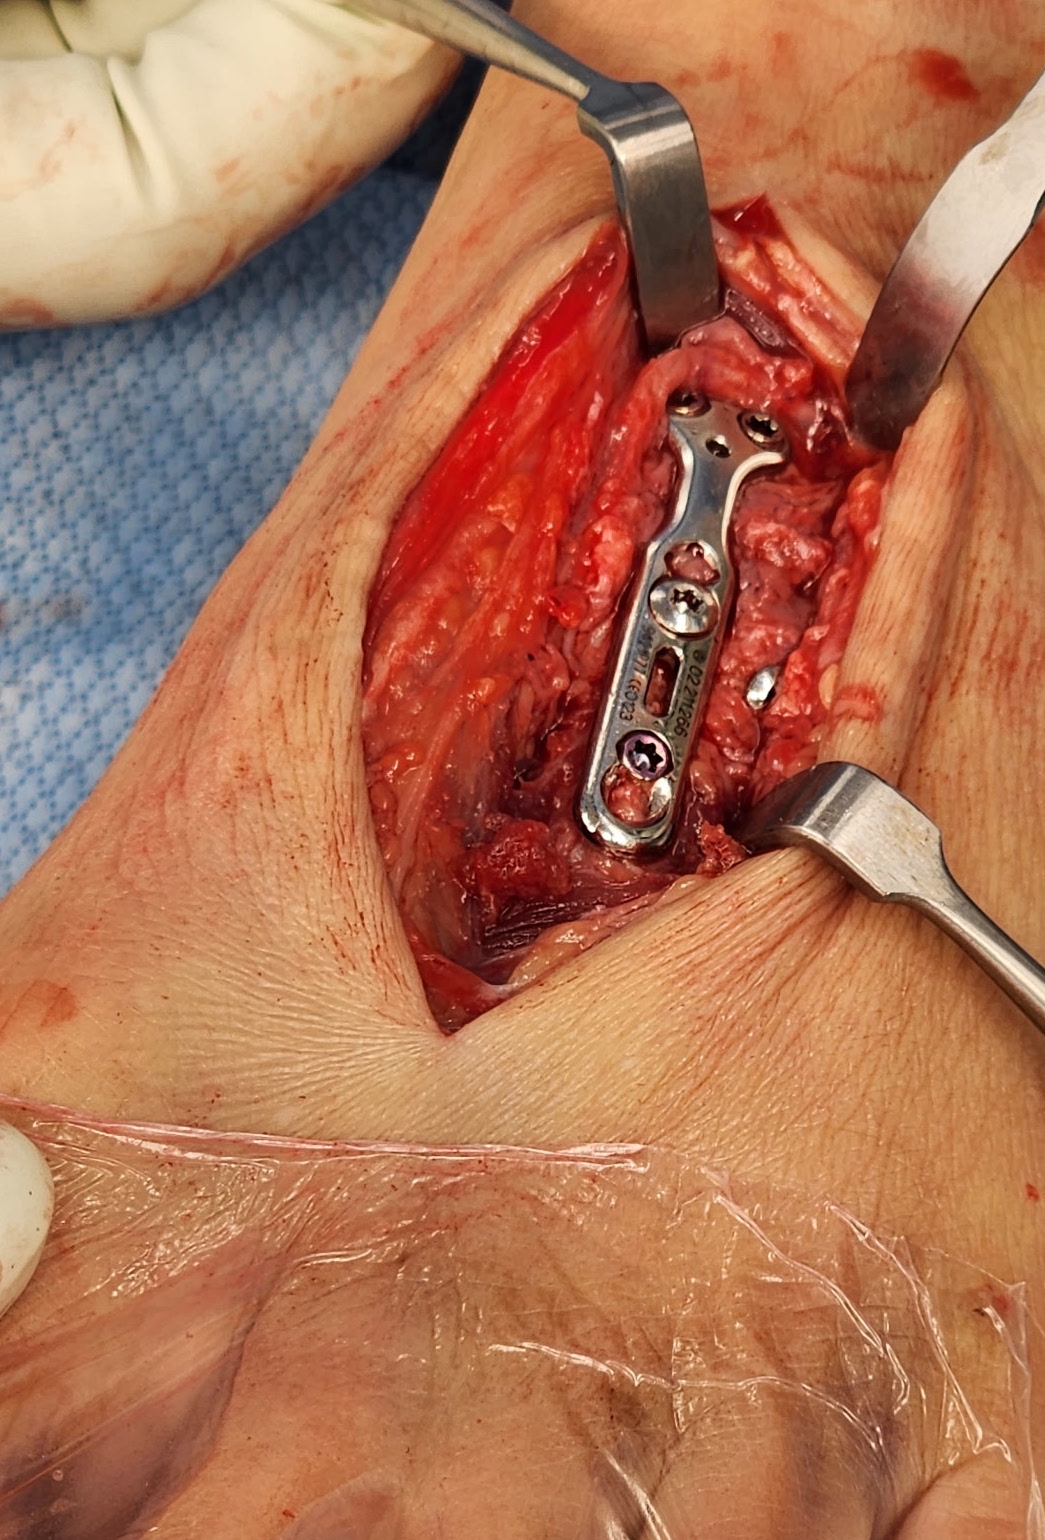

Bridge plate

Advantage

- avoid articular cartilage damage

- avoid broken screws across joint

Bridge plate to 1st TMT and second TMT with Lisfranc screw